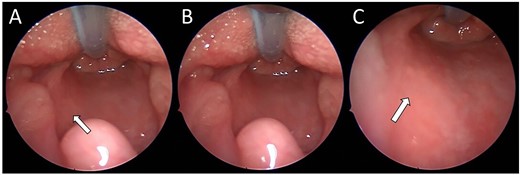

On review of the imaging, the child underwent a biopsy of the lesion for a tissue diagnosis. Direct inspection revealed bulging of tissue from the left parapharyngeal space (Fig. 3). The mucosa was incised, constrictor muscles were divided and incisional biopsies were obtained. Histopathology samples showed lobules of haemangioma, strongly positive for GLUT-1 on immunohistochemistry confirming a carotid sheath infantile haemangioma. The patient continues to be followed up in the outpatient setting.

(A–C) Intra-operative endoscopic photographs highlighting the left sided asymmetric parapharyngeal fullness immediately inferior to the inferior pole of the left tonsil where the biopsy was undertaken and macroscopically abnormal tissue identified.